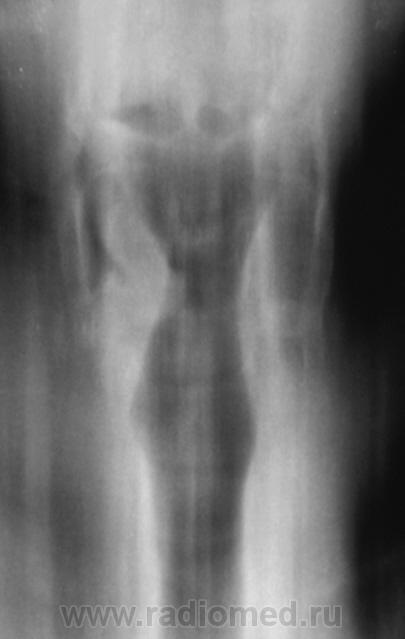

Томография гортани.

Кроме утолщения черпало-надгортанных складок справа, в вестибулярном отделе ни чего не вижу. А что ЛОР видит?